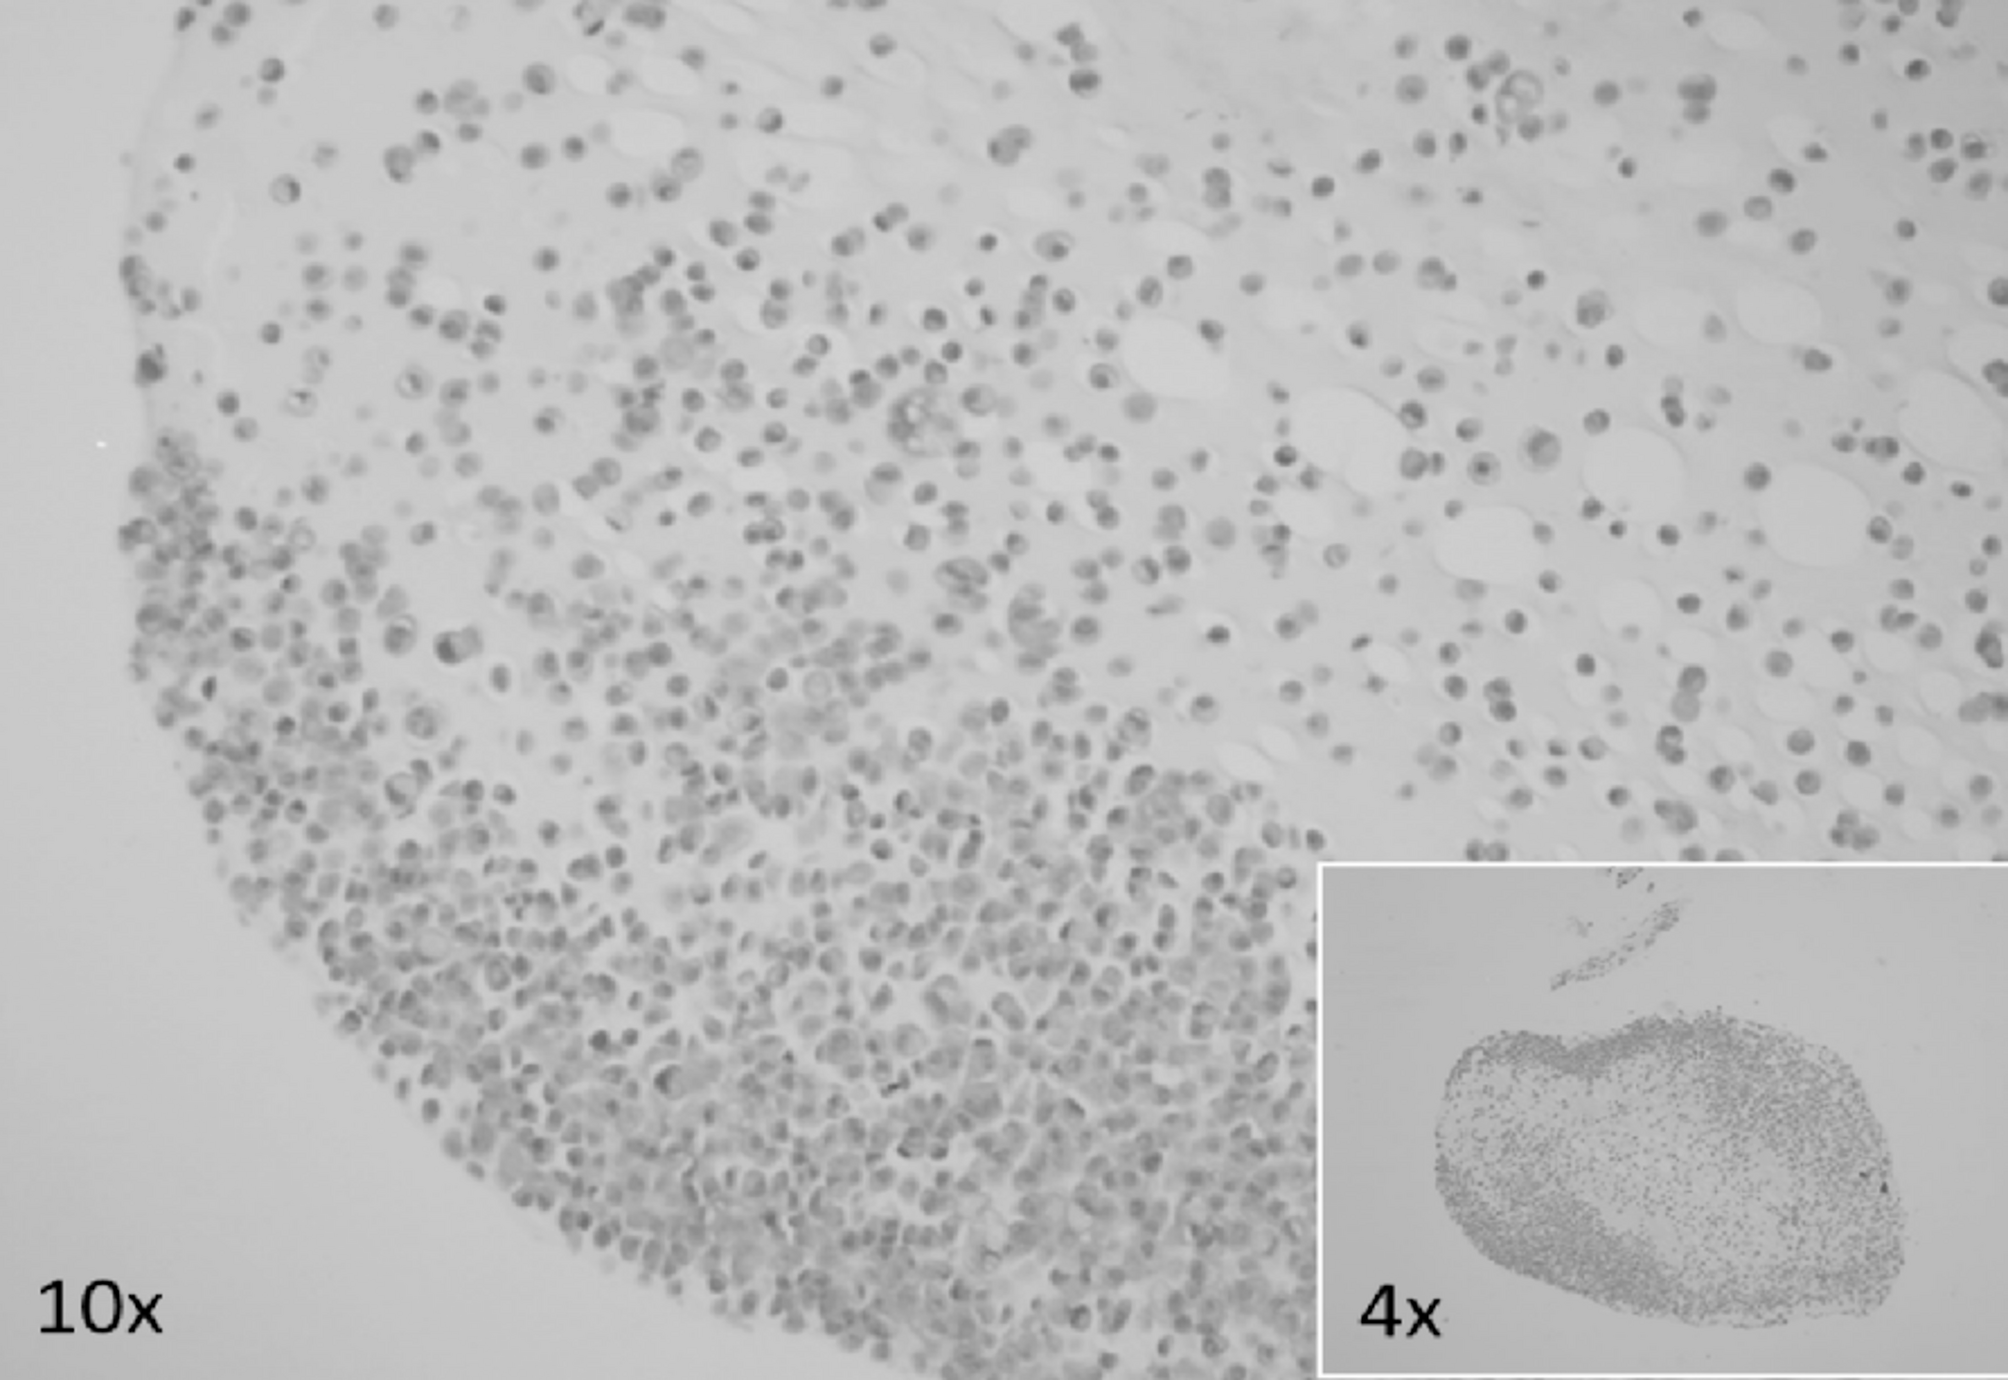

Fig. 6

Alginate-encapsulated cell block slide containing IHG-MUC360 mucoepidermoid carcinoma cells stained with hematoxylin-eosin.